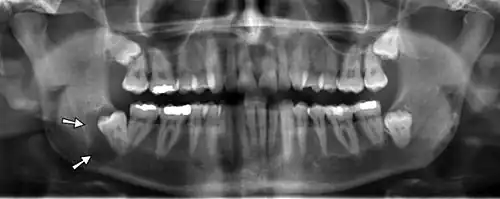

Panoramic radiograph showing Stafne defect (arrowed).

Dental panoramic radiograph showing dentigerous cyst (arrowed).